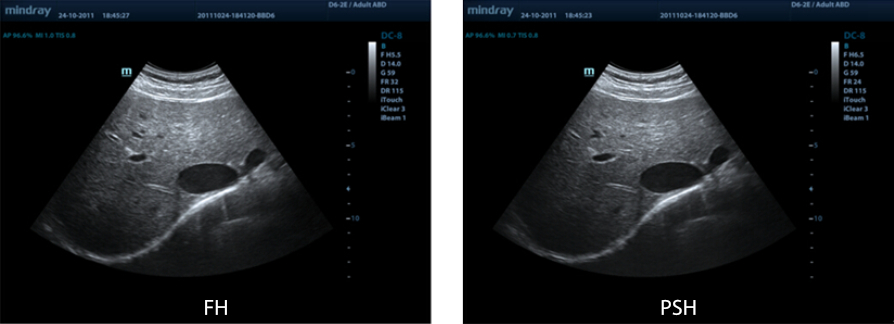

PSHI?(Phase Shift Harmonic Imaging)

PHI (Purified Harmonic Imaging) voor betere contrastresolutie en daardoor duidelijker beelden met uitstekende resolutie en minder ruis

FCI (Frequency Compounding Imaging)

Voor het combineren van verschillende frequenties voor de beste gehele-veldbeeldhomogeniteit, met een betere penetratie speciaal bij hoogfrequente scans